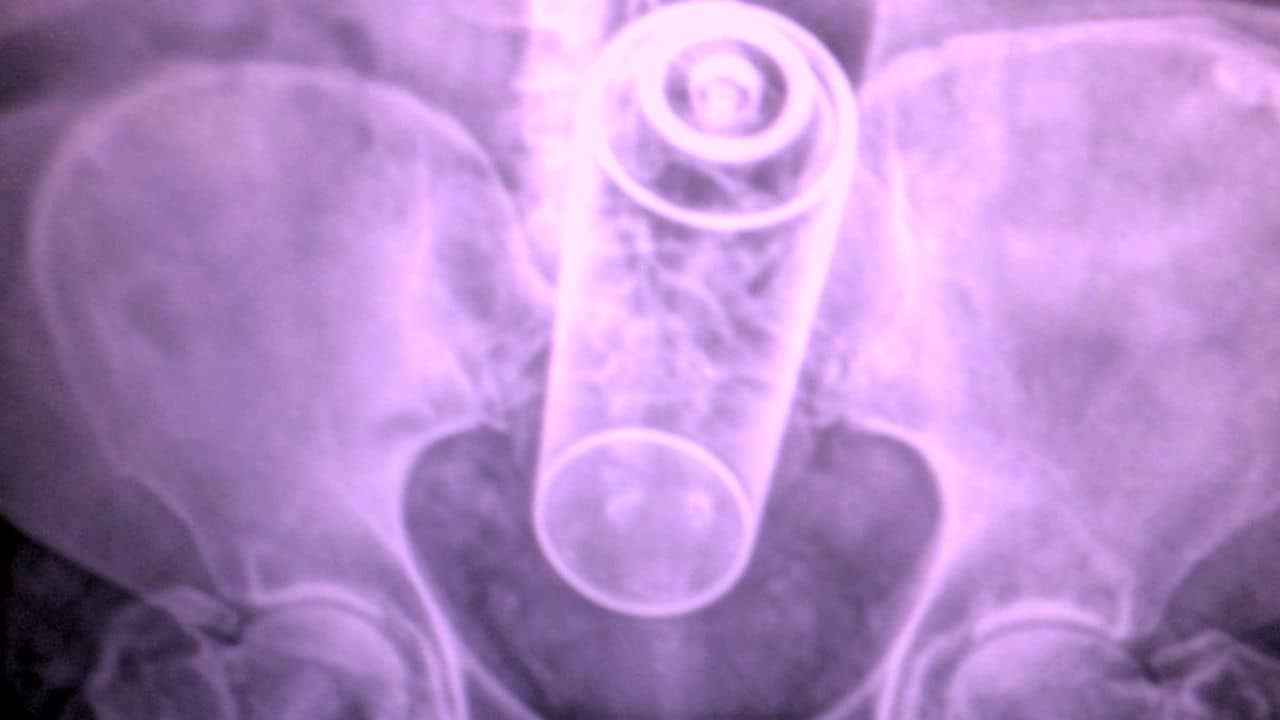

ক্লিনিক্যাল কেস রিপোর্টস জার্নালে প্রকাশিত তথ্য অনুসারে, স্ক্যানে দেখা যায় ওই ব্যক্তির মলদ্বারে প্রায় ১৯ সেন্টিমিটার বা সাড়ে ৭ ইঞ্চির একটি জলের বোতল ঢুকে আছে! ‘রেকটাল ফরেন বডি’ বা মলদ্বারে বাইরের বস্তু ঢুকলে অনেকসময়েই তা বেরতে চায় না। আপৎকালীন পরিস্থিতির সৃষ্টি হয়। কোলোরেক্টাল সার্জারির প্রয়োজনও পড়ে। কিছু ক্ষেত্রে রোগী চিকিৎসা শুরু করাতেও দেরি করেন। সমস্যা আরও জটিল হয়ে যায়। রক্তপাতও হতে থাকে। তবে পঞ্চাশবর্ষীয় ব্যক্তিটি ভাগ্যবান ছিলেন। পরিস্থিতি আরও ঘোরালো হওয়ার আগেই তিনি চিকিৎসা শুরু করাতে পেরেছিলেন।

চিকিৎসকরা সার্জারি ছাড়াই ওই জলের বোতল মলদ্বার থেকে গোটাগুটি বের করতে সক্ষম হন। ধীরে ধীরে বোতল বের করার ফলে অন্ত্রেরও কোনও ক্ষতি হয়নি। জানা যাচ্ছে, ঘটনাটি ঘটেছে ইরানের এক হাসপাতালে। তবে ওই ব্যক্তির রেকটামে কীভাবে বোতলের অনুপ্রবেশ ঘটেছিল তা হাসপাতালের তরফে জানানো হয়নি। অনুমান করা হচ্ছে যৌন ইচ্ছে তৃপ্ত করার উদ্দেশ্যে ওই ব্যক্তি বোতলের মুখ হাতে ধরে পিছনের ভোঁতা অংশটি পিছনে প্রবেশ করিয়েছিলেন। ভেবেছিলেন বোতলের খাঁজযুক্ত মুখটি ধরে বোতলটি বের করতে পারবেন। তবে একসময় তা নাগালের বাইরে চলে যায় ও বৃহদন্ত্রের মধ্যে ঢুকে যায়। ফলে বোতলটিও বের করতে পারেননি তিনি।